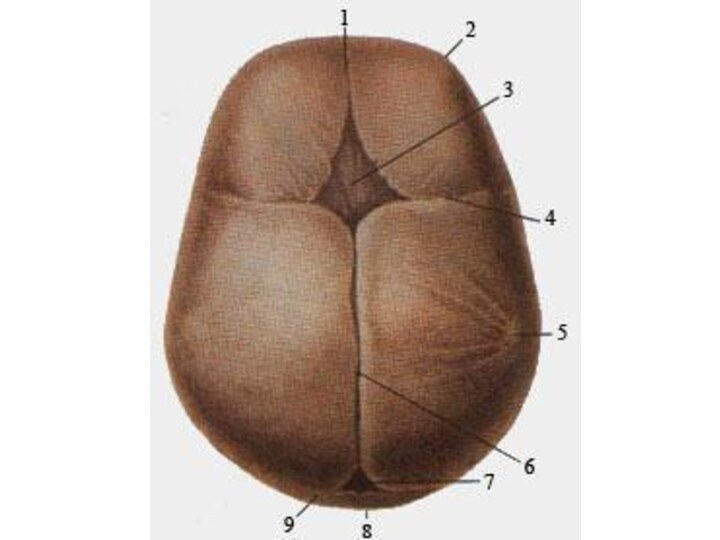

Анатомические изображения срединной сагиттальной линии черепа